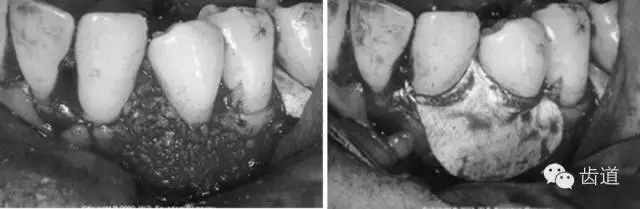

病損區(qū)常規(guī)行牙周翻瓣術(shù),去除感染的牙周袋內(nèi)壁上皮和肉芽組織,根面和骨面清創(chuàng)后,根據(jù)骨缺損和牙根外形選擇并修剪屏障膜,使之能完全覆蓋病損面并固定之,然后齦瓣復(fù)位嚴(yán)密縫合。

3、手術(shù)切口設(shè)計(jì)

需根據(jù)手術(shù)目的、預(yù)后、美觀效果等綜合平衡決定,可根據(jù)患者和病損區(qū)實(shí)際情況靈活選擇溝內(nèi)切口、內(nèi)斜切口、保留齦乳頭切口等,但要注意以盡量保留較多的角化牙齦組織為原則,也即要盡量多保留牙齦乳頭,以保證術(shù)后牙齦能覆蓋膜材料,避免外露導(dǎo)致感染、炎癥等。尤其在鄰面牙間隙處應(yīng)盡量選用齦乳頭保存術(shù)。一般應(yīng)做縱切口和在根方做松弛切口,以保證齦瓣能充分移動(dòng)和避免過(guò)大的張力。